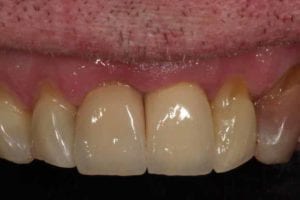

Broken Upper Front Tooth

The upper right central incisor tooth broke and was irreparable. Following removal of this tooth, and implant was placed on the same day as well as a temporary crown. This gave the patient a replacement tooth immediately and after 3 months of healing, a more definitive crown was made to match closely the adjacent tooth.